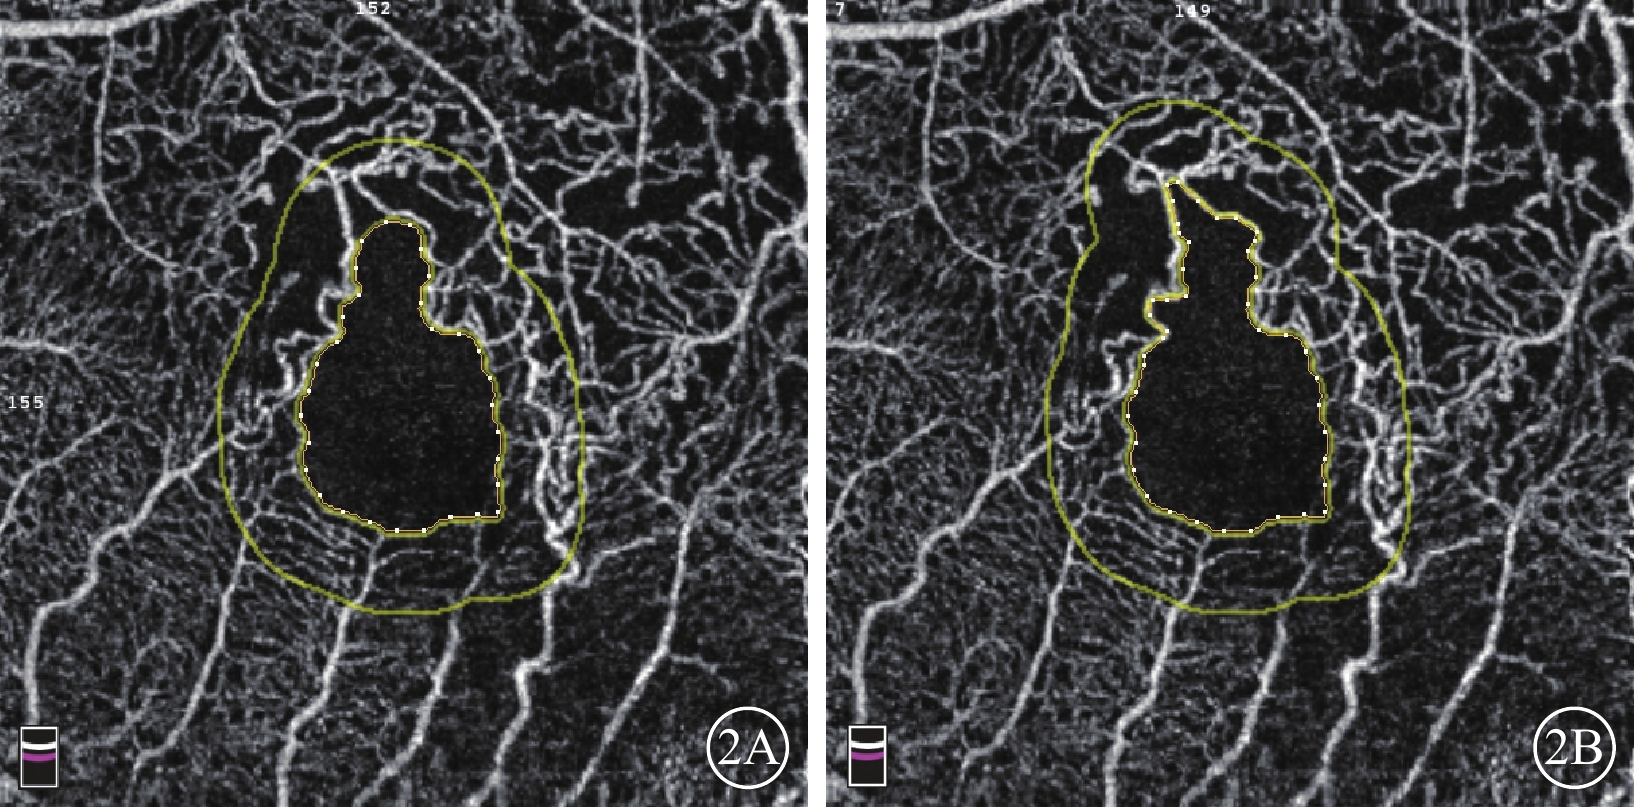

圖2

BRVO患眼OCTA像。2A示軟件自動繪制的FAZ(內圈不規則黃色線內區域),可見拱環上方仍有部分無血管區;2B示手動修改后的FAZ(內圈不規則黃色線內區域)

圖2

BRVO患眼OCTA像。2A示軟件自動繪制的FAZ(內圈不規則黃色線內區域),可見拱環上方仍有部分無血管區;2B示手動修改后的FAZ(內圈不規則黃色線內區域)

圖2

BRVO患眼OCTA像。2A示軟件自動繪制的FAZ(內圈不規則黃色線內區域),可見拱環上方仍有部分無血管區;2B示手動修改后的FAZ(內圈不規則黃色線內區域)

圖2

BRVO患眼OCTA像。2A示軟件自動繪制的FAZ(內圈不規則黃色線內區域),可見拱環上方仍有部分無血管區;2B示手動修改后的FAZ(內圈不規則黃色線內區域)